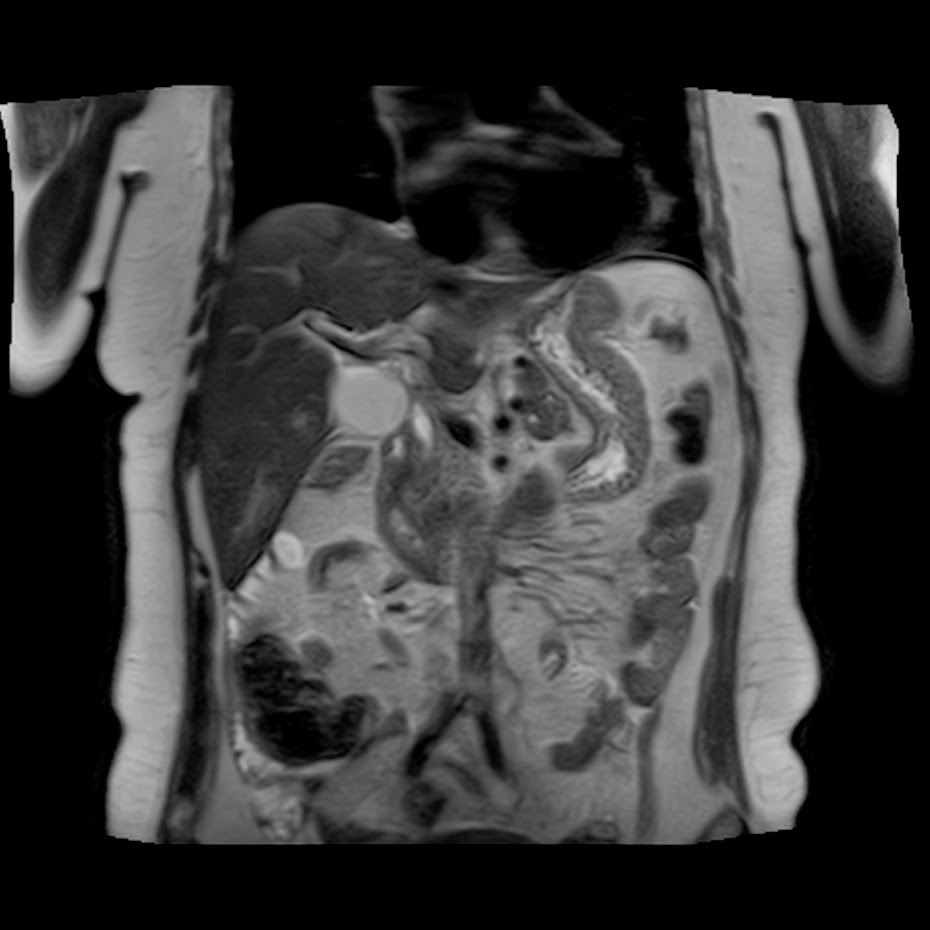

Caso interesante #5

Paciente con dolor en hipocondrio derecho.